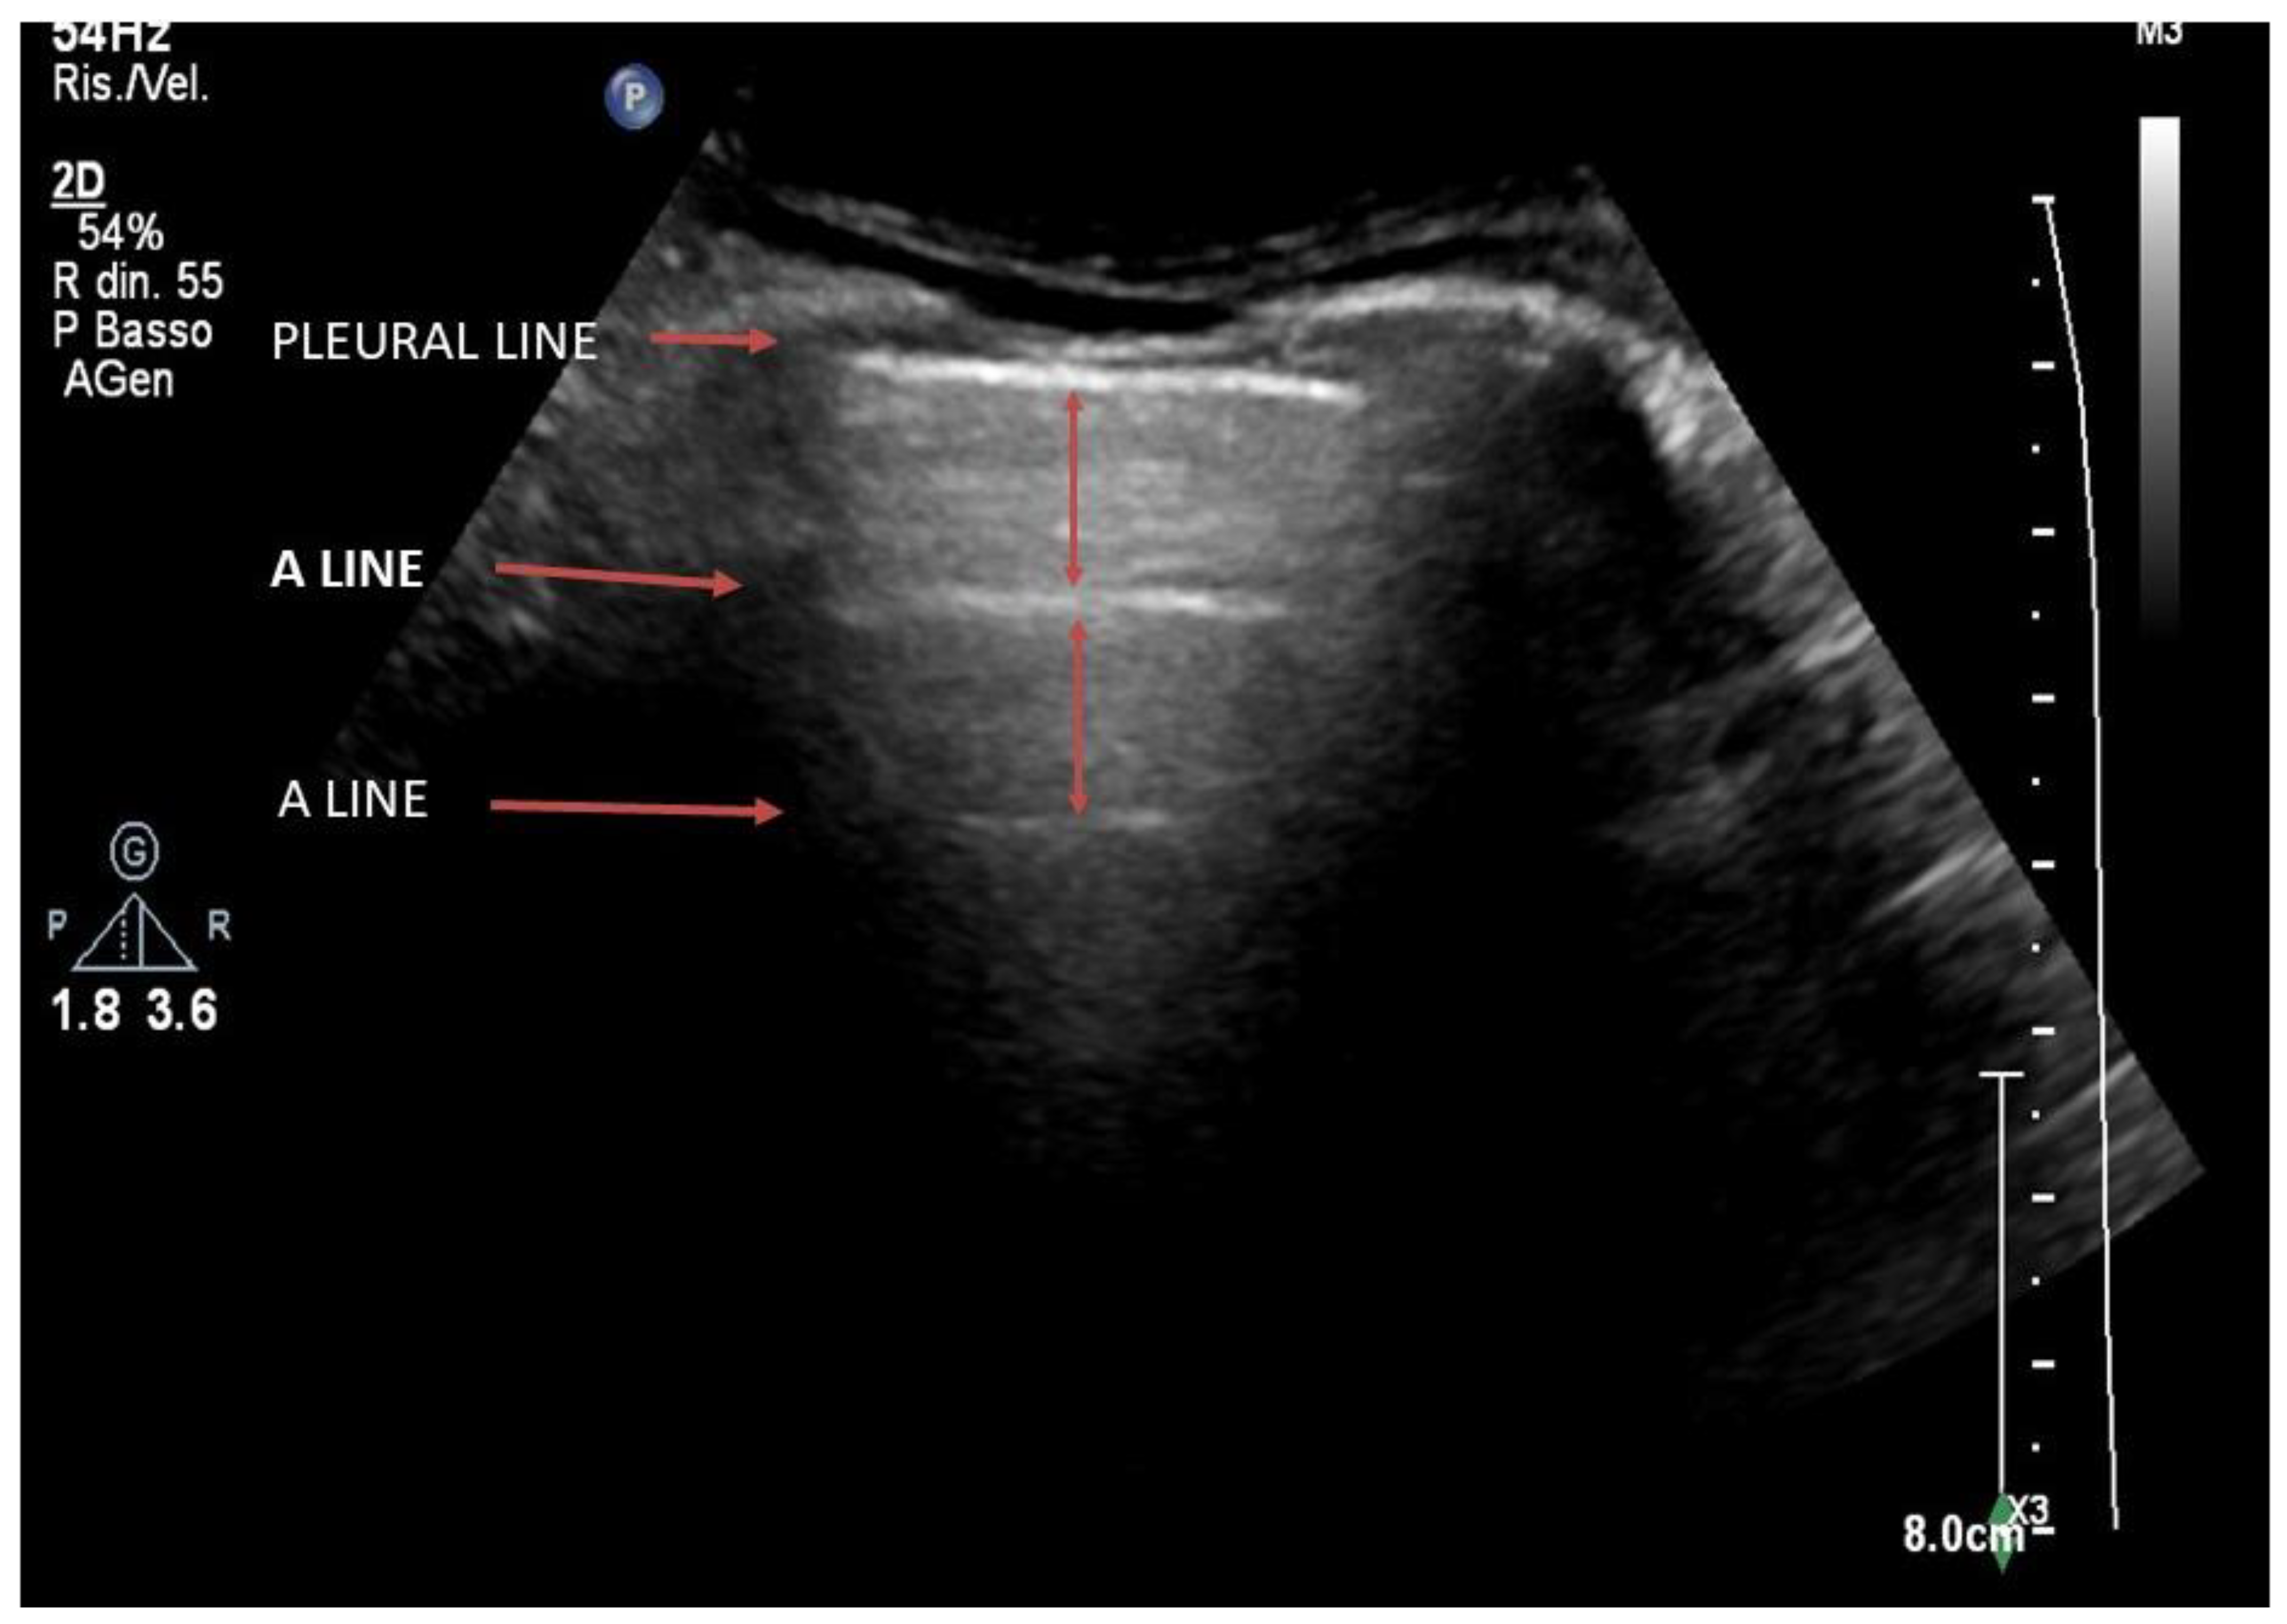

4. Lung Ultrasound on Physiological Lung

3. Lung Ultrasound Evaluation